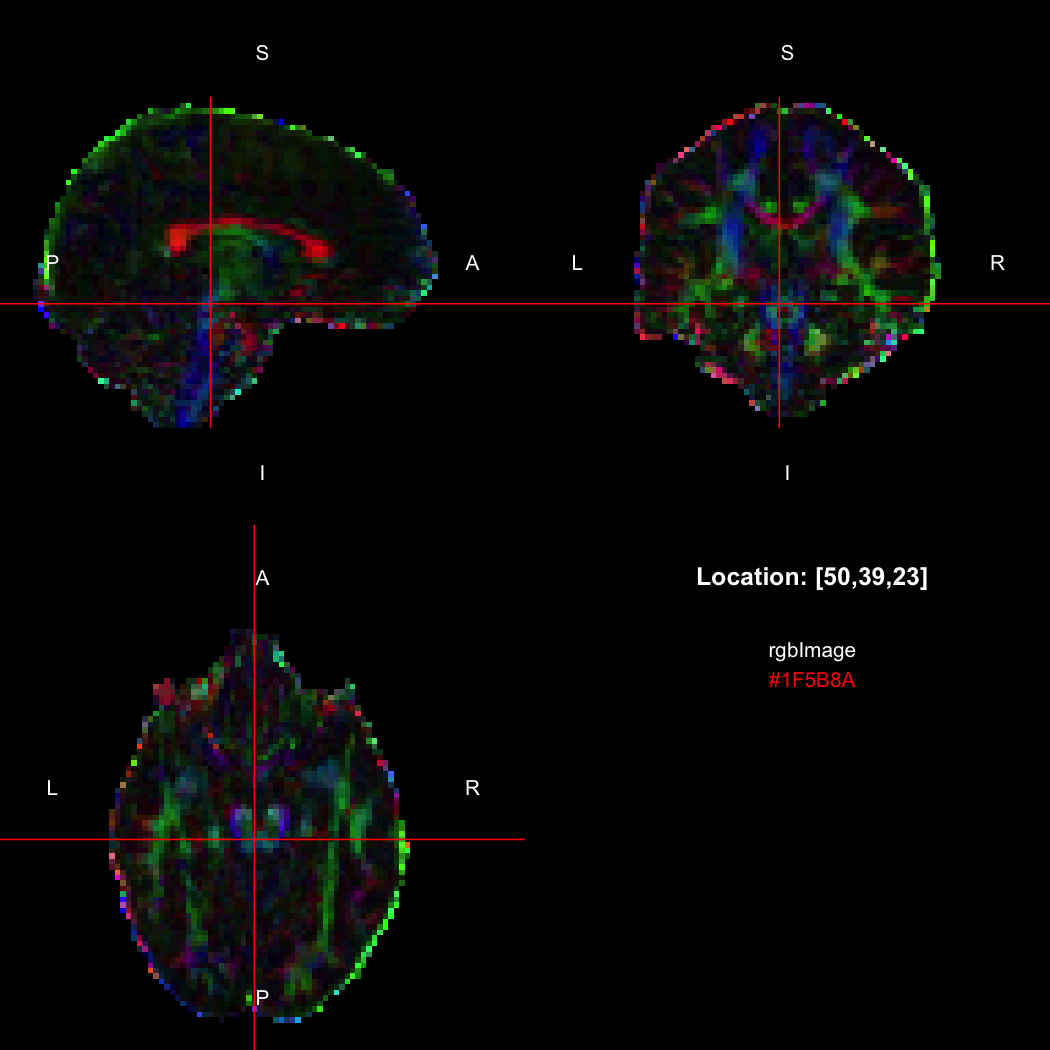

The package contains a basic image viewer, which can be used interactively or noninteractively to examine 2D or 3D images.

view(image)

By default, the viewer shows labels indicating image orientation, crosshairs pinpointing

the currently selected location, the numerical indices of the current

location, and the value of the image at that location. Options allow

each of these to be turned off, for the content of the bottom-right

panel to be customised entirely, for the colour scale to be changed, and

for additional images to be layered on top of the base image. See

?view for details.

rgbImage <- readNifti(system.file("extdata", "example_rgb.nii.gz", package="RNifti"))

print(rgbImage)

## Image array of mode "integer" (2.1 Mb)

## - 96 x 96 x 60 voxels

## - 2.5 x 2.5 x 2.5 mm per voxel

class(rgbImage)

## [1] "niftiImage" "rgbArray" "array"

view(rgbImage)

Notice that values are shown in the viewer using R’s conventional hex

string format, but the data is of class rgbArray. The

function of the same name can be used to create these arrays from

strings or channel values, for the purposes of building RGB images from

data, while the as.character method and

channels function perform the opposite conversions.

as.character(rgbImage, flatten=FALSE)[50,39,23]

## [1] "#1F5B8A"